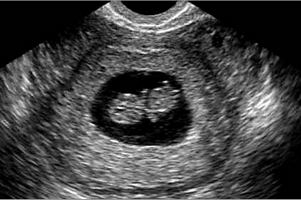

Живіт як і раніше не помітний, хоча матка вже збільшилася настільки, що при огляді гінеколог легко підтверджує наявність вагітності. Якщо ви помітили, що у вас росте живіт - це не через малюка. Просто почався перерозподіл жирових відкладень і у вас страждає травлення, живіт може бути трохи роздутий. Аналізи та обстеження УЗД на цьому терміні легко підтверджує факт перебування жінки в цікавому положенні. Лікар бачить серцебиття дитини (серце скорочується зі швидкістю 110-115 ударів на хвилину). Плодове яйце має розміри близько 2.5 см, КТР зародка близько 5 мм. Аналізи, засновані на визначенні ХГЧ на такому терміні позитивні у всіх жінок. Однак при позаматковій вагітності рівень ХГЧ нижче звичайного, і це є однією з діагностичних ознак.

Ви ніяк не можете здогадатися про те, що носите двійню. Тільки лікар допоможе розкрити цю таємницю. Наявність двох ембріонів на цьому терміні відмінно визначається при ультразвуковому обстеженні або може бути запідозрено гінекологом при огляді.